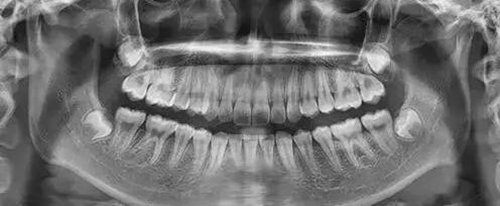

為了幫助矯正醫(yī)生準(zhǔn)確的分析患者的具體情況,醫(yī)生需要幫準(zhǔn)備矯正的患者拍攝全景牙片以及頭顱側(cè)位片。

作用:通過全景片我們可以看到牙齒的數(shù)目是否有異常情況(例如:主要是頜骨內(nèi)有無多生牙,埋伏牙等),牙根的情況(如:包括形態(tài),位置,牙根有無吸收等),牙槽骨的情況,牙周組織的健康狀況,髁狀突的狀態(tài)等。